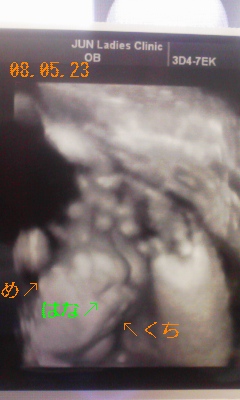

赤ちゃんの推定体重は、3058gに

順調に成長してくれてるみたいで安心